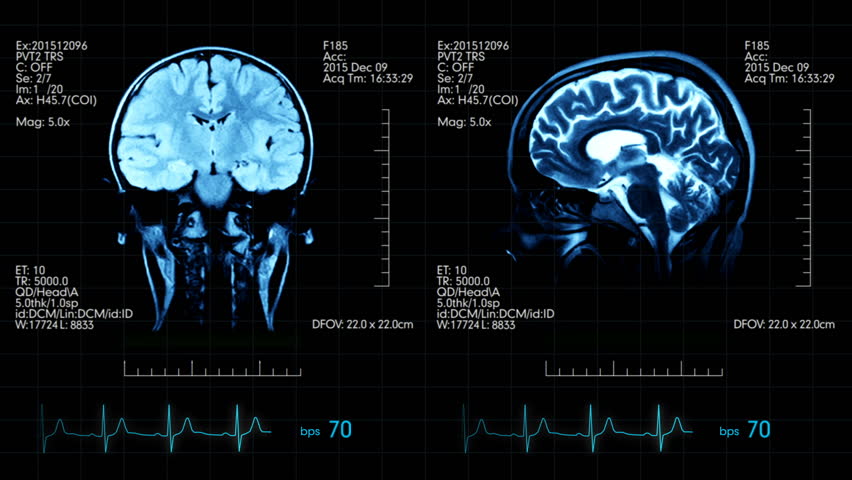

Η ατουκανουμάμπη, η οποία πρόκειται να κυκλοφορήσει στις ΗΠΑ με την εμπορική ονομασία Aduhelm, είναι ένα μονοκλωνικό αντίσωμα που επιτίθεται στο β-αμυλοειδές, μια πρωτεΐνη που συσσωρεύεται στον εγκέφαλο των ασθενών με Αλτσχάιμερ.